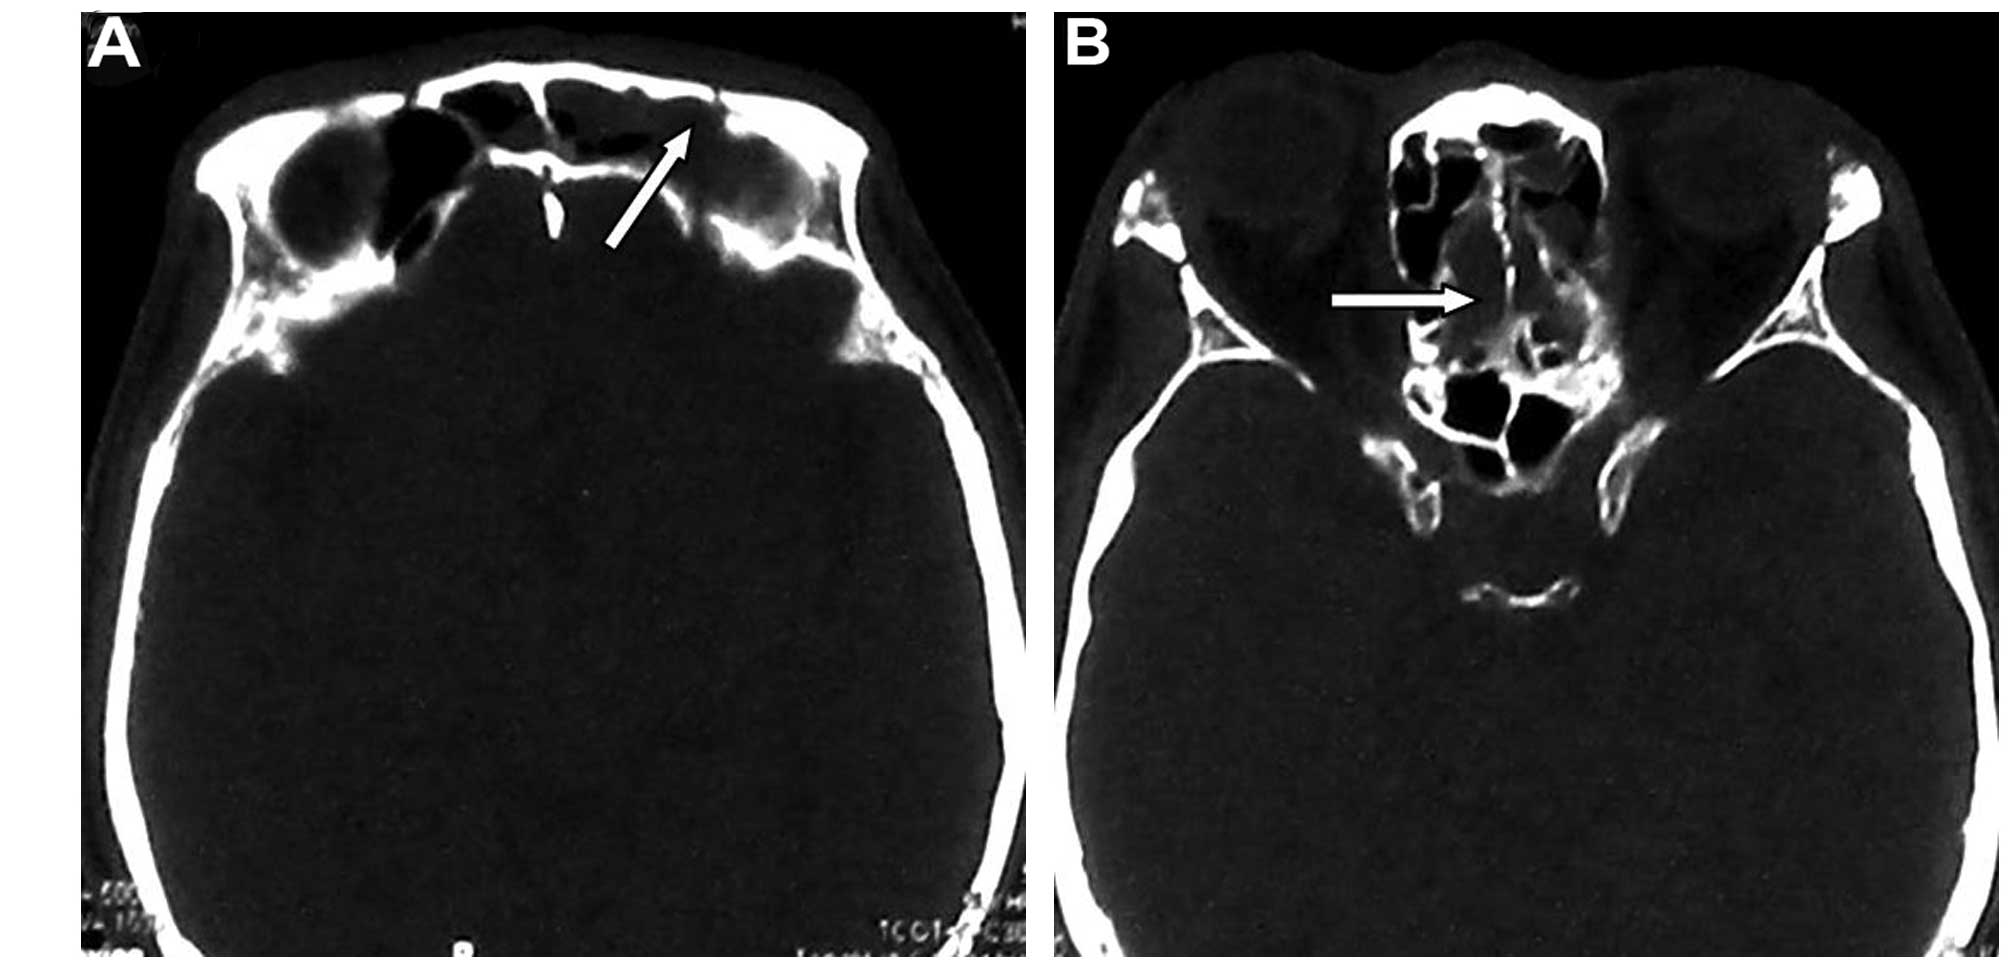

Brainstem edema caused by traumatic carotid-cavernous fistula (TCCF) is rare, and there is little information available regarding its clinical characteristics. The present report describes the case of a 51‑year‑old man with TCCF, who presented with right exophthalmos and intracranial bruit for 1 week. One month prior to admission at hospital, he fractured the frontal and ethmoid sinuses. Digital subtraction angiography confirmed the diagnosis of TCCF, and magnetic resonance imaging (MRI) suggested edema on the right side of the pons. Five days after admission, the patient exhibited left hemiparesis, and MRI revealed aggravation of the brainstem edema. Following treatment with transarterial balloon embolization, the clinical symptoms, including hemiparesis, were relieved; at the 1‑month follow‑up, the brain edema had disappeared. The patient was normal at the 6‑month follow‑up. Following the report of the present case, we reviewed six additional cases previously reported in the literature and discussed the potential mechanisms of TCCF‑associated brainstem edema. We conclude that occlusion of the superior petrosal sinus may contribute to brainstem edema caused by TCCF. Relief of the brainstem edema and brainstem edema‑associated clinical symptoms can be achieved with transarterial coil or balloon embolization of the TCCF to reduce the drainage pressure in the brainstem veins.

Figure 1